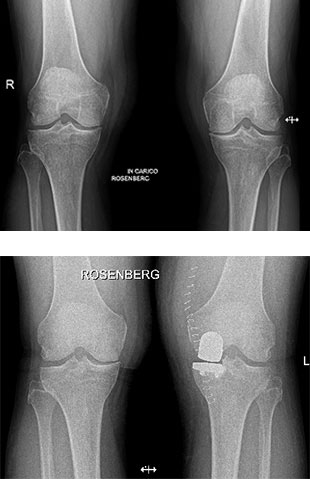

Paziente maschio di 65 anni, affetto da gonartrosi mediale sinistra, trattata con protesi monocompartimentale mediale di ginocchio con tecnica mini invasiva.

Radiografie